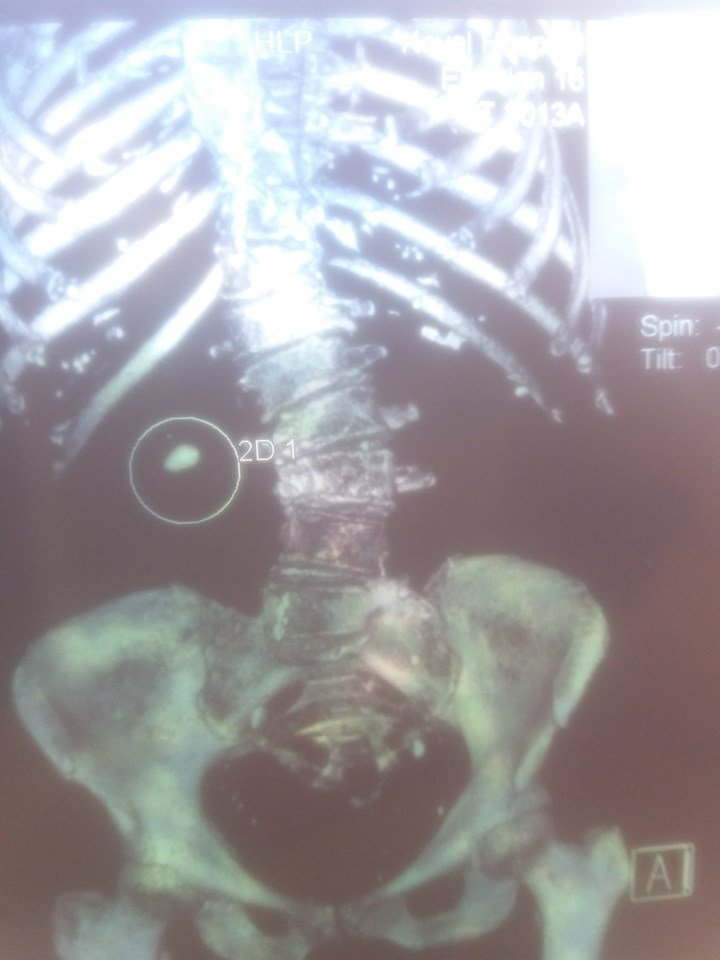

У волинській лікарні пацієнту видалили величезний камінь з нирки. ФОТО

У ковельській лікарні 73-річному чоловіку видалили камінь з нирки.

«Пацієнт 73р, звернувся в центр ендоурології м. Ковеля з великим каменем нирки з супутньою патологією – цукровий діабет і ожиріння», – йдеться у дописі.

Медик зазначив, що чоловіку провели операцію – перкутанна нефролітотрипсія (ПНЛ).

«Камінь подроблено і видалено через один прокол в попереку. Термін перебування в стаціонарі – 4 дні», – пише чоловік.